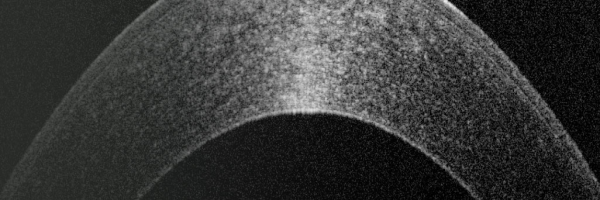

光学相干断层扫描仪(0CT成像)

徕卡光学相干层析成像(OCT)系统以简单易用的高品质成像技术为眼科医生、眼科主刀医生和研究人员提供支持。临床前 OCT解决方案可在眼部疾病研究方面提供深入见解,而临床 OCT 系统可作为诊断病理状况的辅助手段。